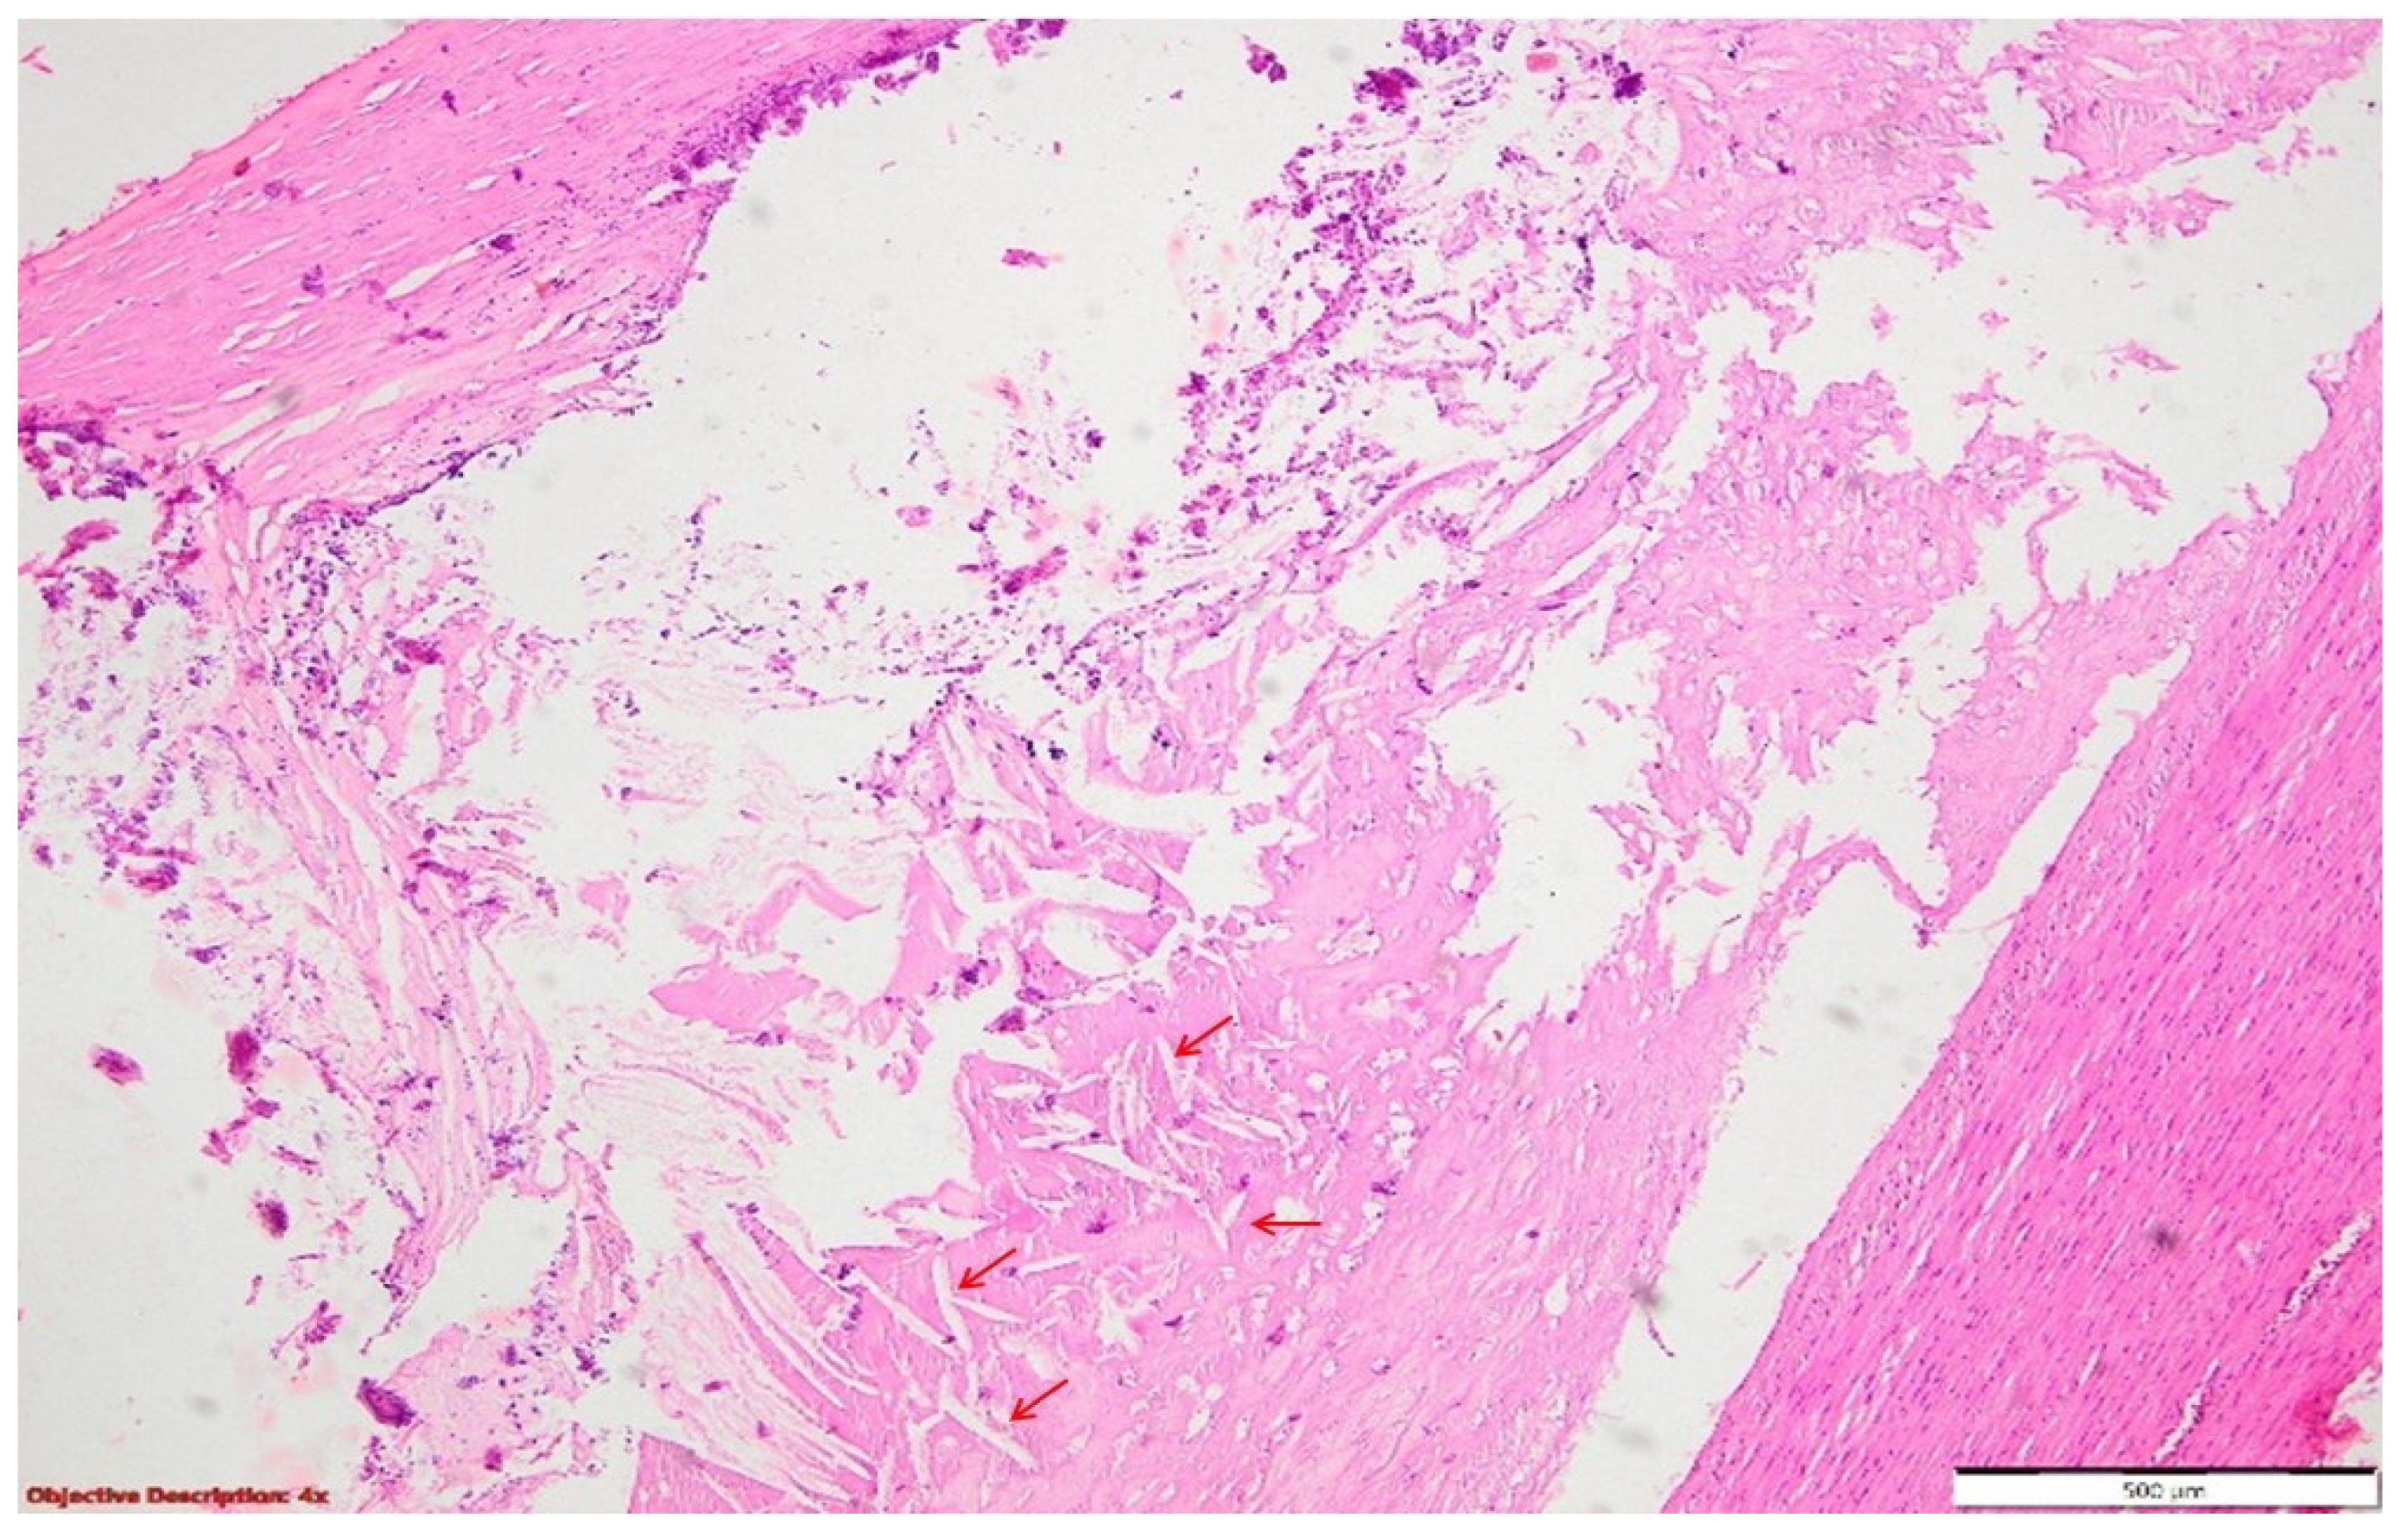

Figure 7. Pulmonary tissue with an enlarged bronchiolar lumen (bronchiectasis →), containing mucus and rare inflammatory elements; smooth muscle hyperplasia of the arterial media, and important polymorphous inflammatory infiltrate (predominantly lymphocytic) in the peri-bronchiolectatic interstitial parenchyma. HE, 40×.